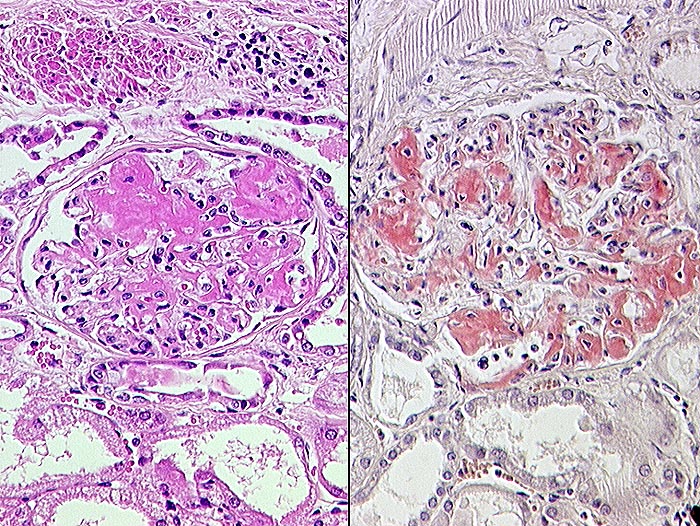

AA-Amyloidose

Systemerkrankung/Immunpathologie

Niere

Rechts: Kongorote Amyloidablagerungen in den Glomeruli.

Links: HE-Färbung.

Multiple Sklerose. Sagomilz.

Histologie